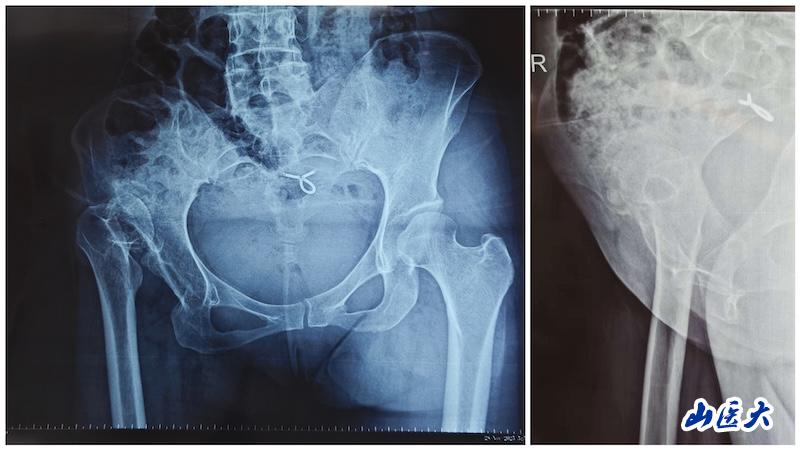

一位中年女性患者长期因髋部疼痛、步态严重异常、双腿长度不一而备受困扰。术前影像显示,其股骨头完全脱位,股骨发育异常,髓腔狭窄,前倾角显著增大,属于关节置换中难度极高的类型。发育性髋关节发育不良(DDH)的Crowe IV型高脱位,一直是对关节外科医生技术的严峻考验。此类手术需同步解决肢体延长、股骨畸形矫正、髋臼-股骨假体重建与软组织平衡等多重难题。

术后影像显示,该患者髋臼重建于真性髋臼,旋转中心得到恢复;股骨侧通过截骨重建,使用普通全涂层假体,同步矫正畸形、恢复偏心距,实现双下肢等长。